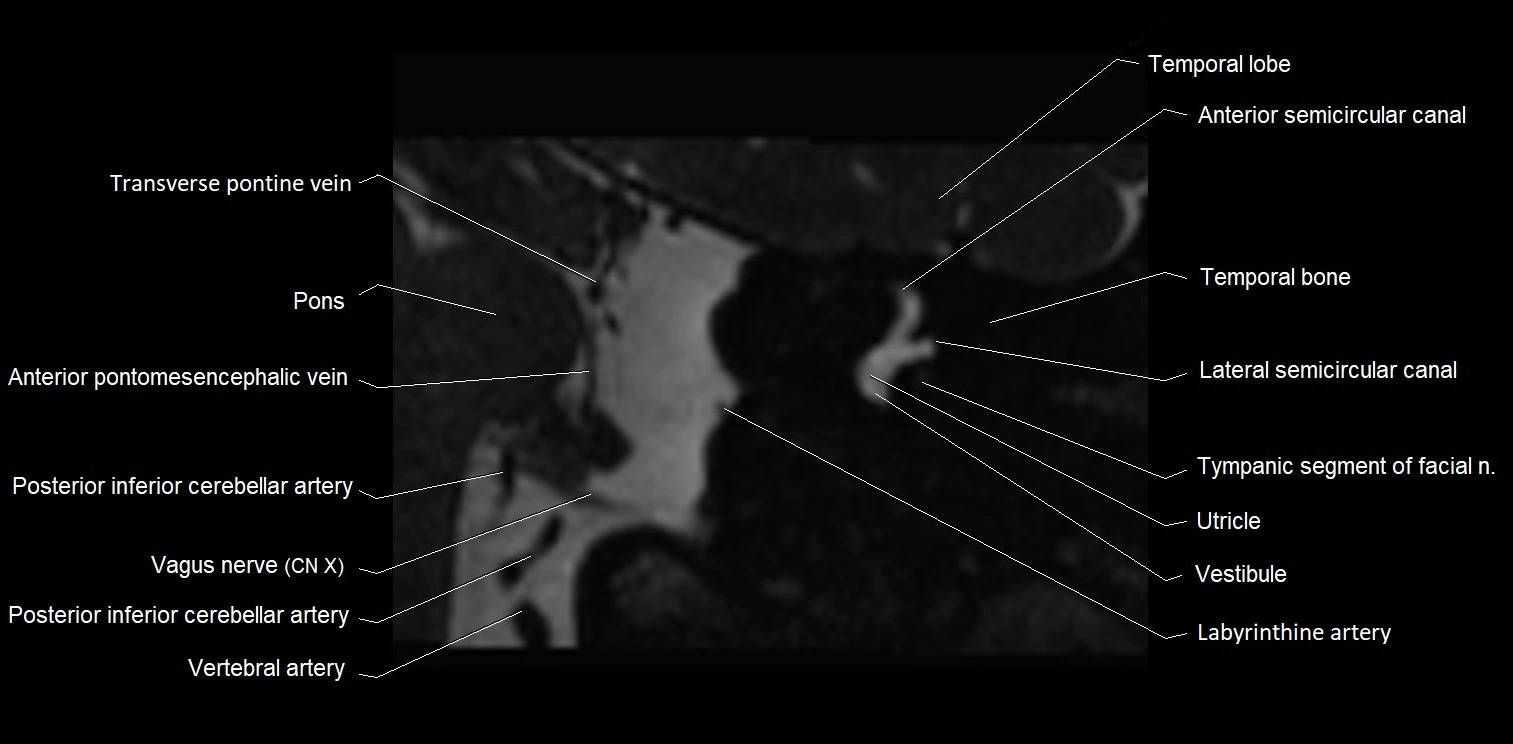

MRI images

image